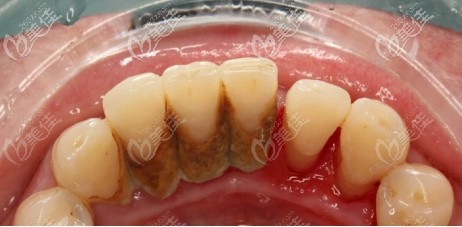

在大部分人的觀念里面,洗牙就是把牙齒表面的臟東西洗干凈,實際上那只是洗牙其中的一部分。其實,洗牙分為齦上潔治和齦下刮治。... b5392 G0 V0

“洗牙”只是一個統(tǒng)稱,在實際的牙科治療中,洗牙分為了4個等級,快來對照看看,你需要的是哪一個級別的洗牙。... b3542 G0 V0